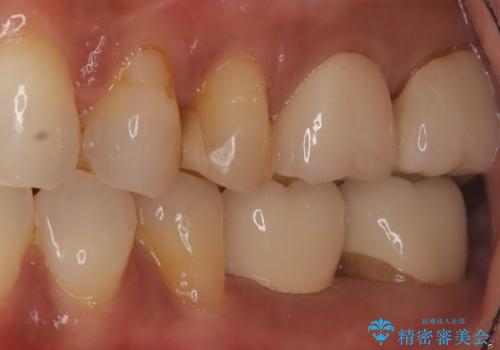

歯の破折 食べる喜びが蘇るインプラント治療

- 歯を破折により失ったため、義歯・ブリッジ・インプラント治療の3つの治療法を提案しました。

骨の量は十分あったため、比較的短期間で治療は終了しました。

安定した咬み合わせとなり、痛みもなく安心して噛めるようになりました。